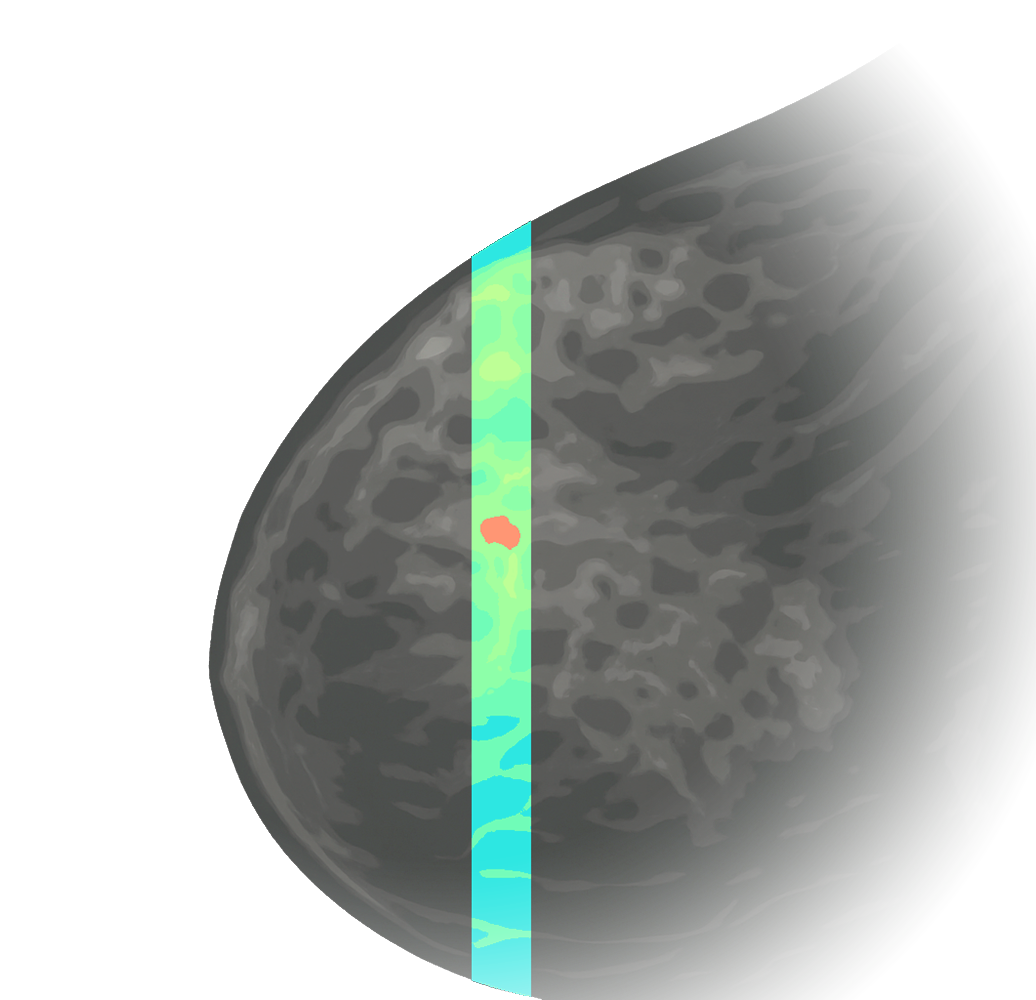

Maps X-ray scatter fingerprints linked to cancer.

At Calidar, we are building next-generation X-ray diffraction imaging to reveal molecular-level signatures of disease. Our patented 4D Mammography technology measures these signatures from the breast noninvasively, providing a new dimension of data with the goal of earlier, more accurate diagnosis of breast cancer.

Maps X-ray scatter fingerprints linked to cancer.